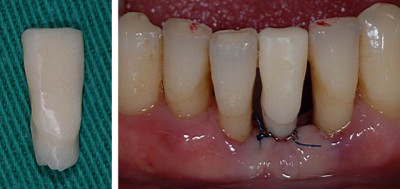

Пациент: 51 год, женщина

Состояние: Пародонтит

#31 шатается, рецессия десны

Продукт: Имплантат для узкого гребня MS

Размеры: Φ 2.5 * 13 mm

Панорамный снимок и фотография ротовой полости